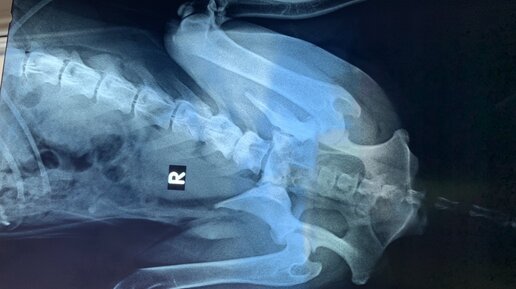

Лечение животных с параличом гортани в условиях отделения реанимации представляет собой сложный и ответственный процесс, требующий профессиональных знаний и опыта ветеринарного врача. Паралич гортани у животных является серьезным состоянием, которое может возникнуть вследствие различных причин, таких как травма, инфекция, опухоль, неврологического дефицита. Это состояние приводит к нарушению функционирования голосовых связок, что приводит к затруднению дыхания и проблемам с обменом газов в организме. При лечении животных с параличом гортани в отделении реанимации необходимо предпринять меры для улучшения дыхания и обмена газов...